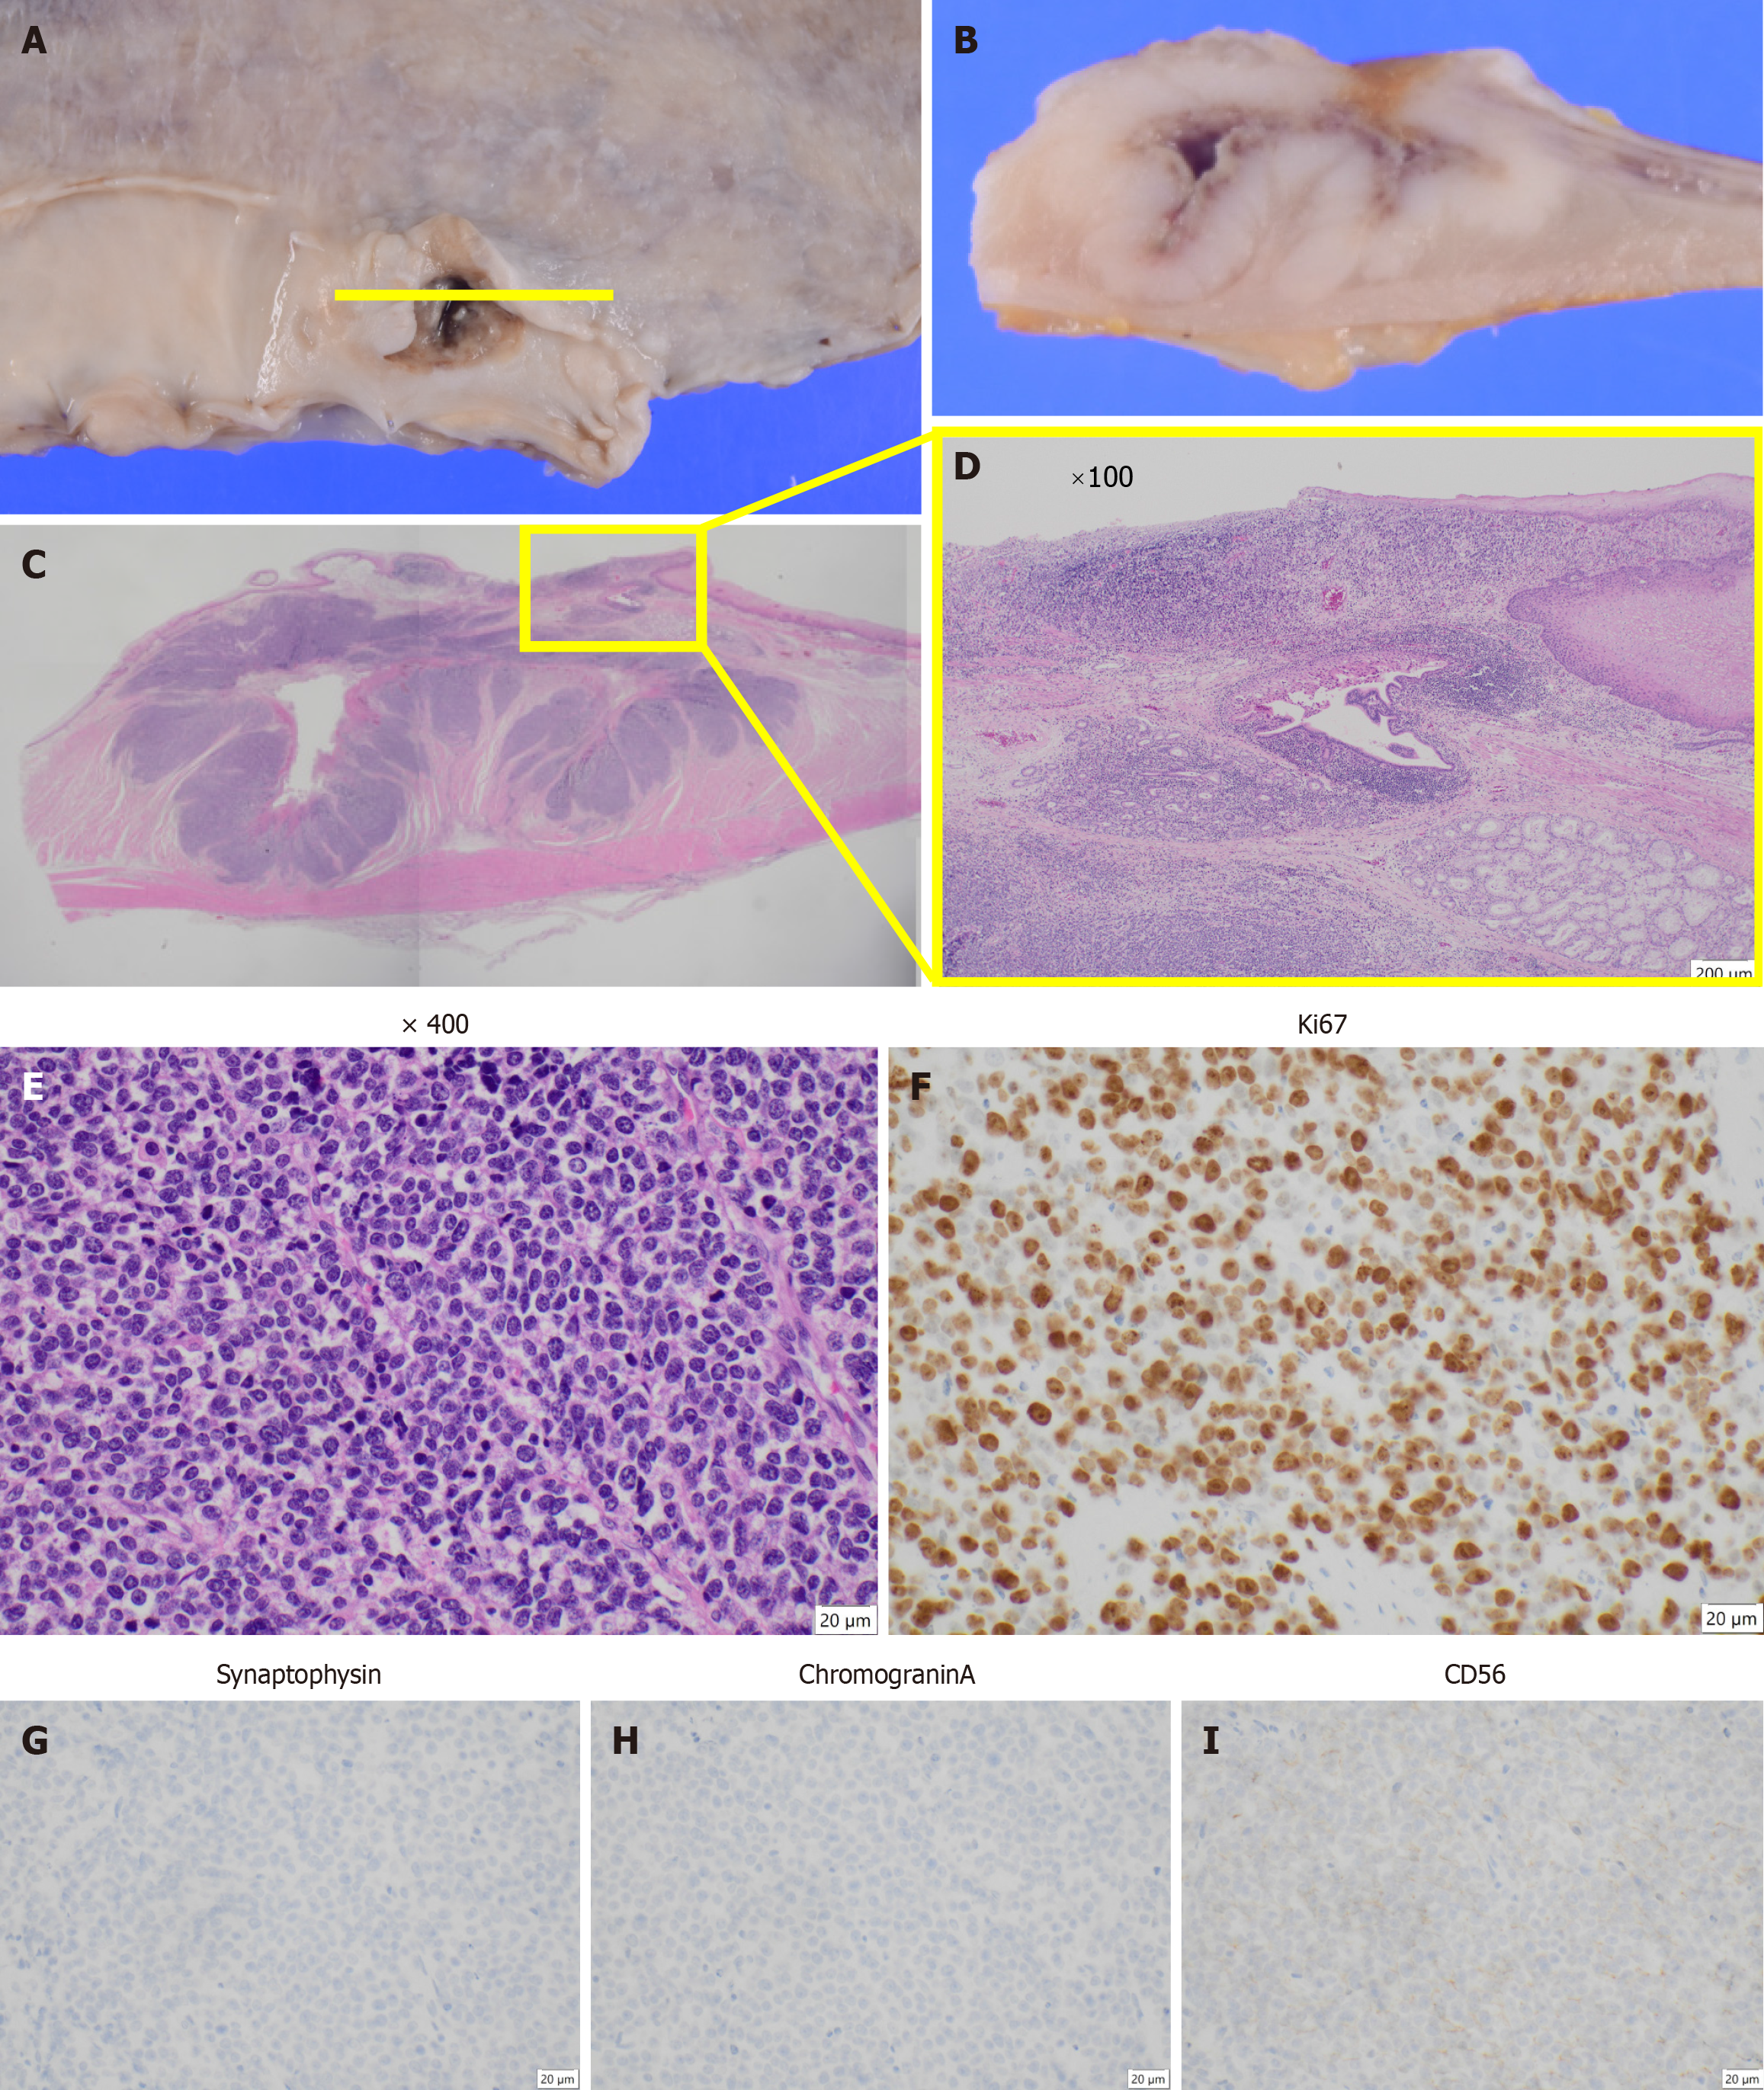

The postoperative pathological diagnosis was NEC, type 5, ypT4aN4 (No. 108, No. 11p) M0 ypStage IVa[10,11]. The resected pancreatic body and spleen showed that the No. 11p lymph node was macroscopically attached to the pancreas. However, pathological examination confirmed the absence of direct infiltration (Figure 4). Histopathological examination of the primary lesion revealed that while multinucleated giant cells and pleomorphic cells were present in the primary lesion, SCC detected before chemotherapy was not observed. Instead, large cell-type NEC was detected. Large pleomorphic cells with a high nucleus-to-cytoplasm ratio formed solid nests and proliferated (Figure 5A-E). Ki-67 staining was positive in more than 90% of the cells. Immunohistochemical staining revealed CD56 (+), chromogranin A

Regarding the diagnosis of NEC, preoperative biopsy often fails to identify this lesion; this is a significant challenges that may influence treatment planning. Histopathologically, NEC frequently coexists with SCC or adenocarcinoma (ADC) within the same tumor[2,12]. A retrospective review of nine surgical cases of NEC at our department between January 2012 and December 2023 revealed three patients who were not diagnosed with NEC preoperatively. Furthermore, postoperative pathology showed association with other histological types in five patients (three with SCC and two with ADC). Because treatment is typically guided by histological diagnosis of biopsy samples in cases where different cancer types are concurrent, treatment may be administered on the basis of non-NEC components, potentially leading to misdiagnosis, especially in advanced, non-surgical cases. Two possibilities can be considered. First, the tumor may have exhibited cellular heterogeneity before treatment, with neuroendocrine differentiated cells present but undetectable in the initial biopsy. These cells might have subsequently proliferated because of their resistance to treatment. Alternatively, neuroendocrine differentiation may have emerged from multipotent cells within the original neoplasm. In this case, histopathological examination of the primary lesion, resected pancreas, and metastatic lymph nodes revealed findings consistent with the therapeutic effects of chemotherapy for the SCC component. However, the minimal change in the size of the enlarged No. 11p lymph node and the therapeutic effect graded as 1a for the primary lesion indicated that the effect on the NEC component was minimal. This suggests the cellular heterogeneity of SCC and NEC.